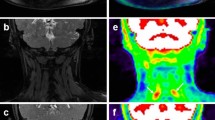

The SUVR obtained from 18F-FP-CIT PET (median [interquartile range (IQR)], 0.86 [0.79 to 0.89]) was significantly lower than that obtained from 18F-flutemetamol PET (0.91 [0.85–0.95], p < 0.001) for overall total brain regions including all cerebral lobes and central structures. In the results for each brain area, the SUVR from 18F-FP-CIT PET for cortical brain regions (i.e., frontal, occipital, parietal and temporal lobes) showed a significantly lower value than 18F-flutemetamol PET (all p < 0.05), with the exception of the central structures (p = 0.232). The detailed results for SUVR are presented in Table 1 and representative images that support these results are shown in Fig. 1.

Representative images of early-phase PETs. The 18F-FP-CIT SUVR image showed less uptake in cortical areas (white arrowheads in A) than the 18F-flutemetamol SUVR image (grey arrowheads in B), while the central structures showed similar activity in the two PETs (white arrows in A and grey arrows in B).